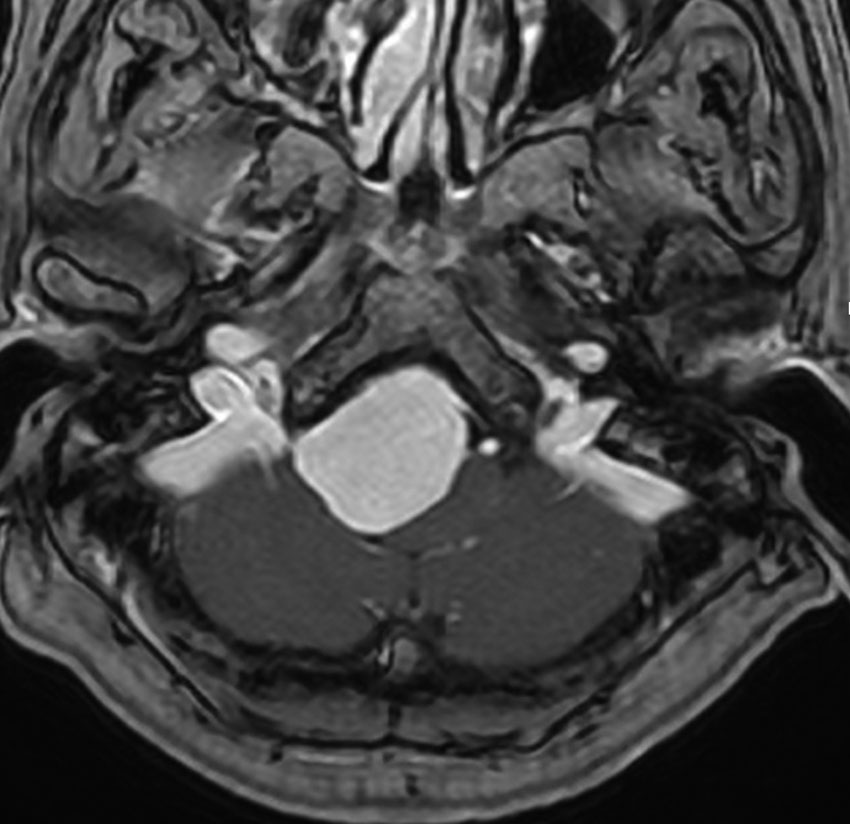

大後頭孔(大孔)髄膜腫 foramen magnum meningioma)

この腫瘍はfarlateral approachなどの頭蓋底手術をしなくても,外側後頭窩開頭で全摘出できます。要領は,S状静脈洞の下端の周囲骨を削除することです。大後頭孔髄膜種は延髄を圧迫するので巨大なものはありません。出血のコントロールや延髄からの剥離は比較的容易なものが多いでしょう。舌咽神経と迷走神経損傷を避けることが重点となります。

迷走神経と舌咽神経は機能温存できました。舌下神経が腫瘍の表面に薄く広がり剥がすことができずに半分以上を切断しています。でも片側舌下神経麻痺では日常生活に困ることはあまりありません。